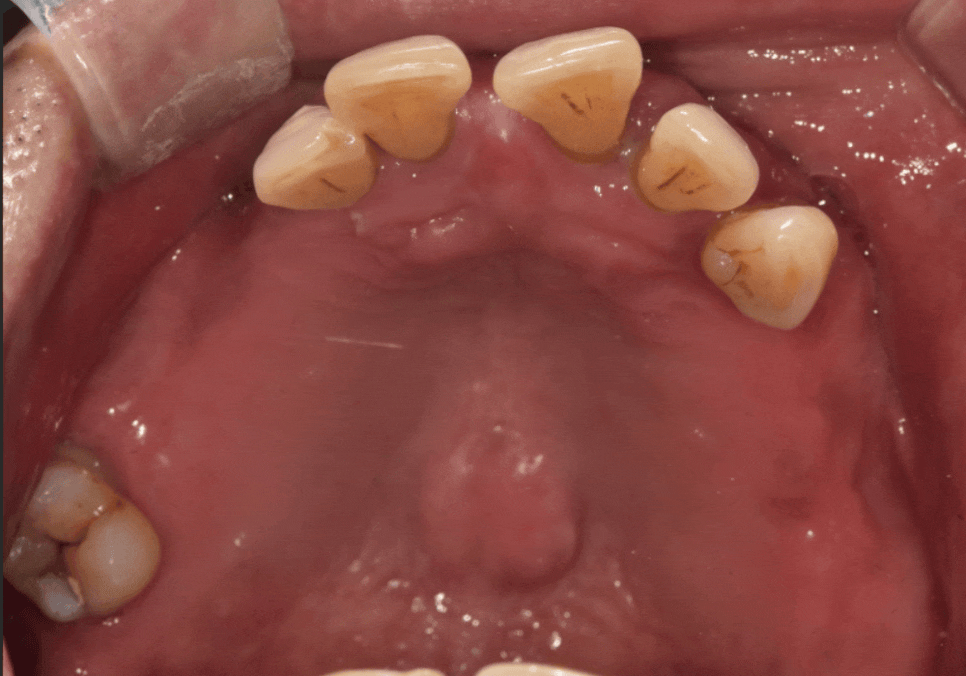

환자분의 구강 상태를 보여주는

파노라마 사진이에요.

언뜻 보셔도 치아가 몇 개 남지 않았다는 걸

금방 아실 텐데요.

위턱과 아래턱 모두 치아가 많이 빠져있고,

그나마 남아있는 치아들도 상태가 좋지 않았습니다.

치아를 잡아주는 잇몸뼈(치조골)가 많이

녹아내려 있었거든요.

특히, 틀니 고리가 걸리는 치아들에

너무 많은 힘이 쏠리다 보니,

뿌리 쪽이 심하게 패어

몹시 약해진 상태였습니다.

이렇게 되면 틀니를 아무리 새로 맞춰도

잇몸만 아프고 제대로 씹기가 참 힘듭니다.